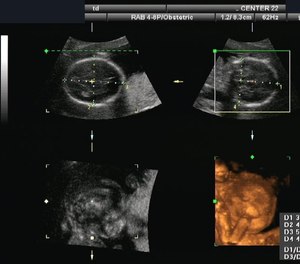

Ultrasound systems have been mainstream medical devices since the mid-1960s, with significant imaging improvements occurring with each decade.

Ultrasound devices as medical tools have been around since 1942, when neurologist Dr. Karl Theodore Dussik first used sound waves to detect brain tumors. Ultrasound systems have been mainstream medical devices since the mid-1960s, with significant imaging improvements occurring with each decade.

Over the past 20 years, portable machines have brought point-of-care ultrasound capabilities to physicians in emergency departments, introducing improving rapid diagnostic capabilities and improving skills performance. The question then arises, can and should paramedics be using these devices outside of the hospital? In the past year, the answer from experts in the field is a resounding, “Yes!”

A systematic review of literature on prehospital point of care ultrasound (P-POCUS) concluded, “Prehospital POCUS is feasible and changes patient management in trauma, breathing difficulties and cardiac arrest, but it is unknown if this improves outcome.” Clearly more research is required, but the introduction of new smaller, lighter, more EMS-friendly devices coincides with positive experiences of EMS services already successfully using P-POCUS to rapidly diagnose and treat challenging patient presentations.